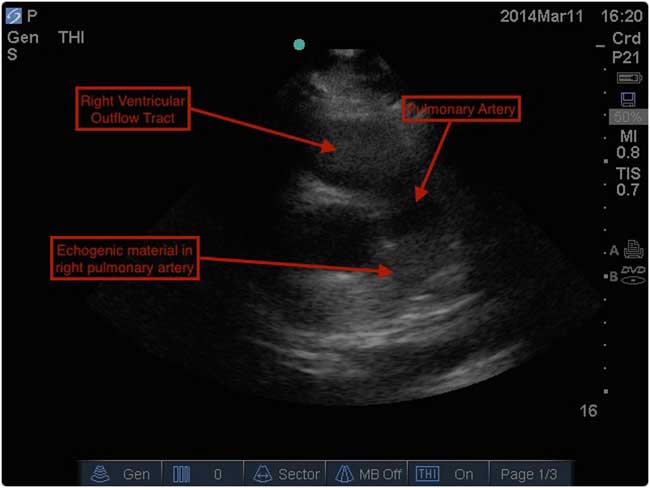

In addition to the previously listed PoCUS findings, bedside diagnosis of PE is based on the visualization of a thrombus in the right heart as has been described.Reference Sharifi, Berger and Beeston 19 While this particular finding was not noted during resuscitation in our case, a subsequent review of our patient’s bedside ultrasound images did reveal echogenic material in the right pulmonary artery (Figure 3). Clinically, the presence of a grossly abnormal right ventricular shape and function on PoCUS contributed significantly to our immediate treatment decisions. It is important to note that bedside echocardiography alone cannot safely rule out PE.Reference Konstantinides, Torbicki and Agnelli 5 , Reference Squizzato, Galli and Gerdes 13 Nevertheless, the presence of particular findings on PoCUS in the context of a suspicious clinical presentation may strongly suggest the diagnosis.Reference Squizzato, Galli and Gerdes 13 Other than a visible clot, specific echocardiographic findings reported in patients with PE are all consistent with right ventricular (RV) strain or overload: increased RV size, decreased RV function (both noted in our case), and tricuspid regurgitation.Reference Come 14

Figure 3 PoCUS still image showing echogenic material, suspicious for clot, in the patient’s right pulmonary artery.